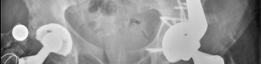

(Figs. 19.22, 19.23, and 19.24)

Fig. 19.22 Most recent routine follow-up PA pelvis, prior to emergency department presentation. Evidence of significant femoral peritrochanteric and pelvic periacetabular osteolysis